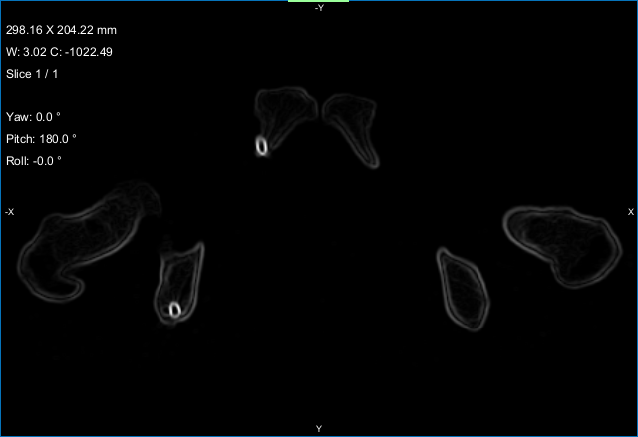

Lets you chose the settings that will be applied to generate a mesh surface from all selected paths in the paths list. You should note that unselected paths will be excluded from all calculations.

Mesh surface settings